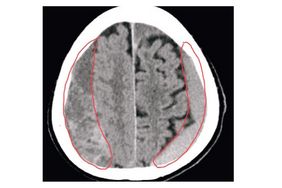

Ein „Chronisches Subduralhämatom“ (cSDH) ist eine Blutung im Kopf, die an der Gehirnoberfläche zwischen harter und weicher Hirnhaut entsteht – typischerweise bei älteren Patienten. Auslöser kann schon ein leichtes Trauma sein, begünstigt wird es durch blutverdünnende Medikamente. Das Hämatom bleibt oft lange unbemerkt, kann aber, wenn es wächst, zu neurologischen Ausfallerscheinungen, Arm-/Beinschwäche und Sprachstörungen führen.